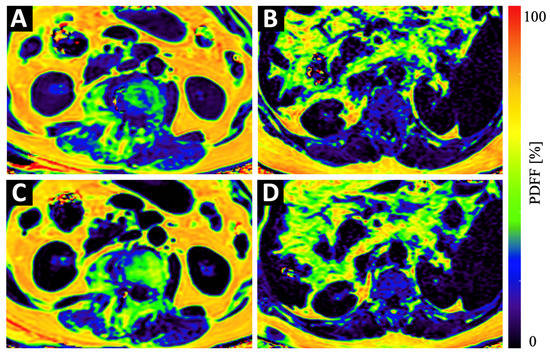

Figure 3.

Example color-coded PDFF maps of a 84-year old osteopenic (BMD = 107 mg/cm3) female patient (A,C) and a 69-year old male patient with normal BMD values (123 mg/cm3) (B,D) at baseline (A,B) and 6 months follow-up (C,D). Although the maps of the osteopenic patient (A,C) show a strong increase in PDFF in vertebral bone and in the PSM, the increase in the maps of the non-osteopenic/osteoporotic patient (B,D) show only a very subtle increase in PDFF.